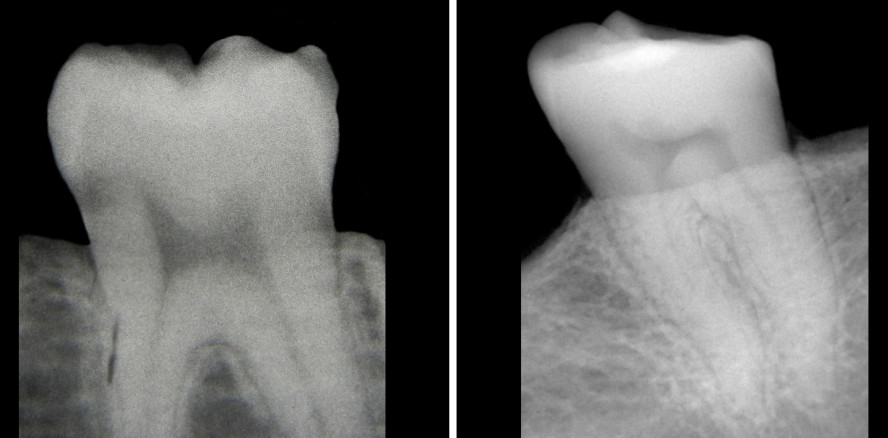

Foto: McMaster University

Wie es um die eigene Vitamin-D-Versorgung bestellt ist, lässt sich anhand von Zahnröntgenaufnahmen ablesen, wie kanadische Forscher herausfanden.

Nun haben Forscher der McMaster University jedoch einen Weg gefunden, einen Mangel an Vitamin D anhand der Zähne abzulesen – ohne sie dabei aufspalten zu müssen. Möglich wird dies, weil ein eindeutiger Zusammenhang zwischen dem Vorhandensein des Vitamins und der Pulpaform ausgemacht wurde. Der Vorteil: Ein unkompliziertes Ablesen mithilfe von Röntgenaufnahmen wird realisierbar.

Zeigt die Zahnpulpa eine gerade Form, die einem Stuhl ähnelt, kann man von einem starken Vitamin-Mangel ausgehen. Ein geschwungener Verlauf mit „Hörnern“ sagt hingegen, dass alles in Ordnung ist.